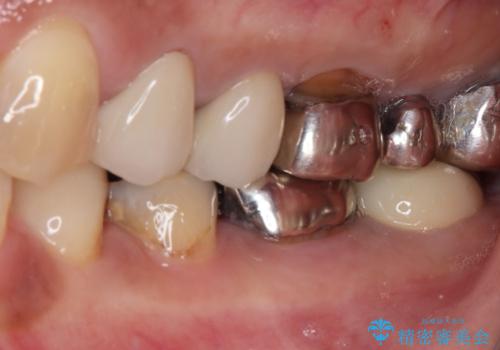

- 銀歯の奥が欠けてしまったとのことで来院された患者様です。

大きな銀歯が装着されており、その下からむし歯が広がっている状態でした。

特に症状はなく、神経組織も健全な状態であったため、むし歯を全て取り切った後にフルジルコニアクラウンにて補綴することとしました。